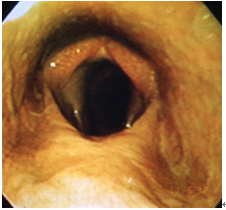

喉頭片麻痺(喘鳴症、のど鳴り)

反回神経の異常が原因で、披裂軟骨の外転に必要な背側輪状披裂筋(CAD)と内転に必要な外側輪状披裂筋(CAL)に萎縮・変性が起こることで発症します(図2)。運動時に喘鳴音(ヒューヒューという高い音)が聞こえ、パフォーマンスが非常に低下するのが特徴です。さらに病状は進行性で、披裂軟骨の外転不全による部分的な上気道の閉塞が起こり、吸気性の呼吸困難に陥ることがあります。確定診断は安静時での内視鏡検査で行います。さらに最近では運動時内視鏡検査を実施し、より詳細な検査が行われています。治療として、喉頭形成術(Tie-back)と呼ばれる披裂軟骨を外転させ固定する外科手術を行います。さらに声帯切除術も合わせて実施することもあります。

2_17

図2 喉頭片麻痺